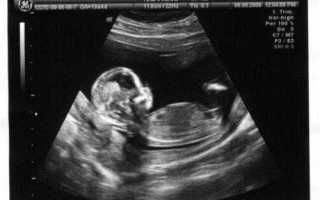

В 12 недель беременности большинство женщин направляются на скрининговое УЗИ. Это исследование отличается важностью, так как помогает оценить развитие и общее состояние плода. Посредством УЗИ можно спрогнозировать возможные патологии.

Качество диагностики также зависит от класса аппарата. При использовании современного экспертного сканера можно получить больше информации. Сделать фото возможно, если аппарат имеет функции 3D, 4D.

В 12 недель беременности можно определить количество плодов в полости матки, регистрировать их сердцебиение и движения, которые указывают на жизнедеятельность. Плодное яйцо в 12 недель беременности не измеряют вследствие его большого размера.

На темп роста плода указывает КТР. Этим термином называют отрезок от нижней точки копчика до верхней части темечка.

Специалист также оценивает развитие внутренних органов и состояние плаценты. Её толщина в 12 недель составляет 14.5-15.5 миллиметров. Особое значение имеет визуализация косвенных признаков возможных патологий хромосомного характера, например, синдрома Дауна.

Данные признаки называют маркерами. Существует два основных маркера:

- толщина воротниковой зоны: 1.6 (0.8 2.4),

- длина носовых косточек: 2.3 (1.8 2.9).

Косвенные признаки грубых аномалий развития можно определить при увеличении толщины шейной складки ил уменьшение дины носа, его отсутствие.

В процессе выполнения УЗИ специалист также оценивает состояние яичников, шейки матки, цервикального канала с целью исключения угрозы выкидыша и патологий репродуктивной системы.